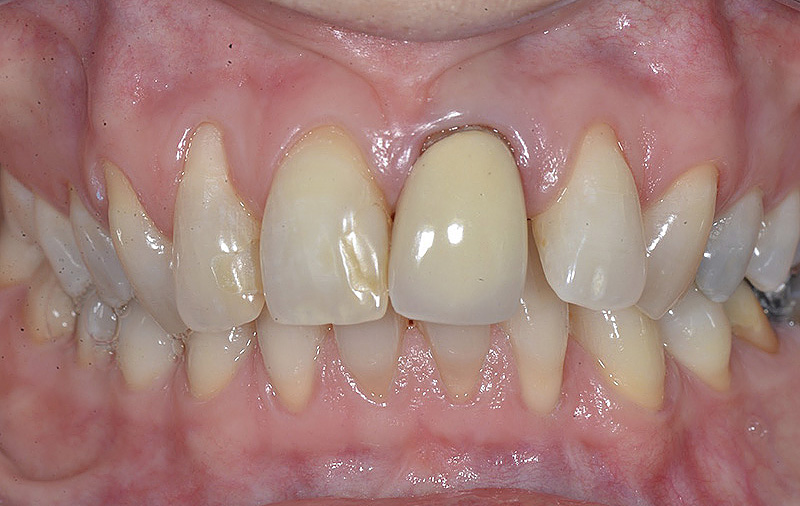

PREMESSA: in seguito all’estrazione dell’incisivo laterale superiore di destra, resasi necessaria per cause batteriche, si decide di affrontare il caso con il posizionamento di un impianto in sostituzione dell’elemento mancante dopo guarigione del sito infetto. Con tecniche rigenerative sia dei tessuti ossei mancanti a causa dell’infezione pregressa, sia dei tessuti gengivali che appaiono inizialmente troppo spostati in alto, si ripristina una corretta morfologia delle parabole (contorni) gengivali e delle papille interdentali (triangoli di gengiva tra due denti vicini).

Vengono utilizzati 2 tipi di provvisori: il primo, cementato ai denti vicini, viene utilizzato dal momento dell’estrazione del dente fino ad impianto osteointegrato (circa 6 mesi); il secondo, avvitato direttamente all’impianto, ha una funzione di prova estetica ma soprattutto di guida per la maturazione dei tessuti gengivali peri-implantari portandoli verso la maturazione completa prima di posizionare la corona finale in disilicato di litio.